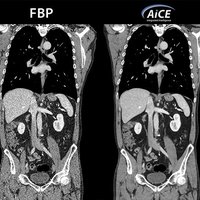

Mit AiCE, kurz für Advanced intelligent Clear-IQ Engine, kann der Aquilion One PRISM Edition besonders scharfe, klare und präzise Bilder in kürzester Zeit gewinnen. Die KI unterstützt die Reduktion von Bildrauschen auf ein Minimum und ermöglicht klare Aufnahmen mit sehr gut erkennbaren Strukturen auch bei niedrigem Kontrast. Gleichzeitig bringt sie eine automatische Anpassung des Kontrasts mit sich. Weiterhin ermöglicht sie eine schnelle kV-Umschaltung und eine patientenspezifische mA-Modulation, die wiederum mit einer Deep Learning-Rekonstruktion kombiniert wird, um eine hervorragende Energietrennung zu erzielen und Bildrauschen weiter zu reduzieren.